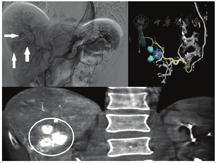

尽管术前影像检查可以显示病变的位置,但难以轻易识别出供应肿瘤的特定肝动脉分支的数量和位置[23]。90Y微球选择性内放射治疗前常需要肝动脉全景造影用于确保剂量送至病灶,从而最大程度地提高疗效并减少潜在的非靶器官栓塞。直接肝血管造影术(图1)是在连续透视下用造影剂注入肝动脉及其分支,医师可清晰观察到肿瘤、肿瘤的血供及可能供应其他器官的任何分支。特别是胃十二指肠和右胃动脉也可能来自于肿瘤供应动脉起点远端的肝分支。在治疗前,可以预先栓塞供应其他器官的动脉,以防止90Y微球误放置至肝外的其他区域,引起严重的不良反应[24]。此外,还可使用锥形束CT和引导软件优化90Y选择性内放射治疗前的肝动脉显示,从而清晰显示肿瘤及其血供分支(图1)[25]。